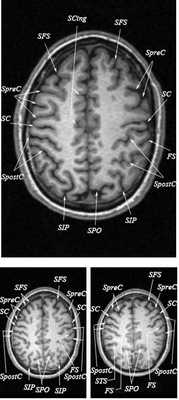

Знание анатомии мозга очень важно для правильной локализации патологических процессов. Ещё более важно оно для изучения самого мозга с помощью современных «функциональных» методов, таких как функциональная магнитно-резонансная томография (fMRI), и позитронно-эмиссионная томография. С анатомией мозга мы знакомимся ещё со студенческой скамьи и существует множество анатомических атласов, в том числе и поперечных сечений. Казалось бы, зачем ещё один? На самом деле, сравнение МРТ срезов с анатомическими приводит к множеству ошибок. Это связано как со специфическими особенностями получения МРТ изображений, так и с тем, что строение мозга очень индивидуально.

Представленная страница сайта основана на специальном изучении МРТ головного мозга здоровых лиц. Для этого изображения получали с минимальной величиной воксела (1 мм в каждом измерении), что исключало наслоения борозд. Каждая из структур прослеживалась в трёх реконструированных плоскостях путём её выделения с помощью компьютерной программы. Мы рассматривали различные анатомические варианты, что обсуждается в работе. В результате, учитывая вариабельность строения мозга, подобран условно «стандартный» мозг. Поскольку на сайте нереально представить 128 срезов в каждой из основных плоскостей, мы ограничились только каждым пятым срезом. Основные срезы в поперечной плоскости даны без наклона назад (угол 0º). Под ними для представления о изменении соотношения анатомических структур демонстрируются срезы, выполненные на тех же уровнях, но с наклонами назад -15º и -30º.

Список сокращений

Борозды

Междолевые и срединные

SC - центральная борозда

FS - Сильвиева щель (латеральная борозда)

SPO - теменно-затылочная борозда

SCing - поясная борозда

SpreC - предцентральная борозда

SFS - верхняя лобная борозда

SpostC - постцентральная борозда

SIP - внутритеменная борозда

STS - верхняя височная борозда

Поперечные (аксиальные) МРТ срезы головного мозга